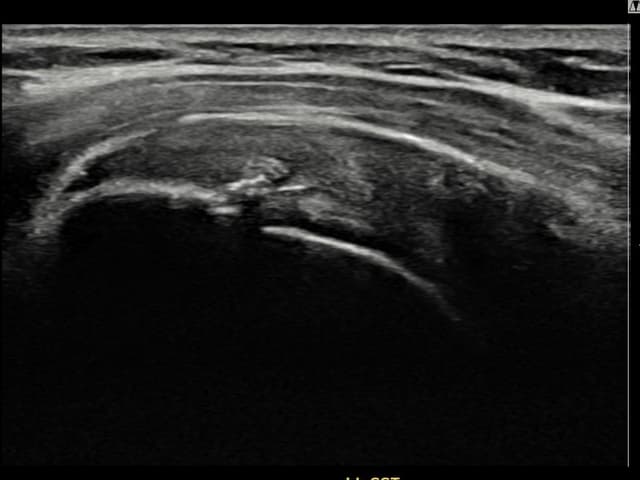

[촬영시기:24.09.05~24.11.14]

[어깨인대 축소봉합술] 우측 어깨 통증으로 팔을 들어올리기 어렵고 취침 시 통증이 심해 내원하셨습니다.